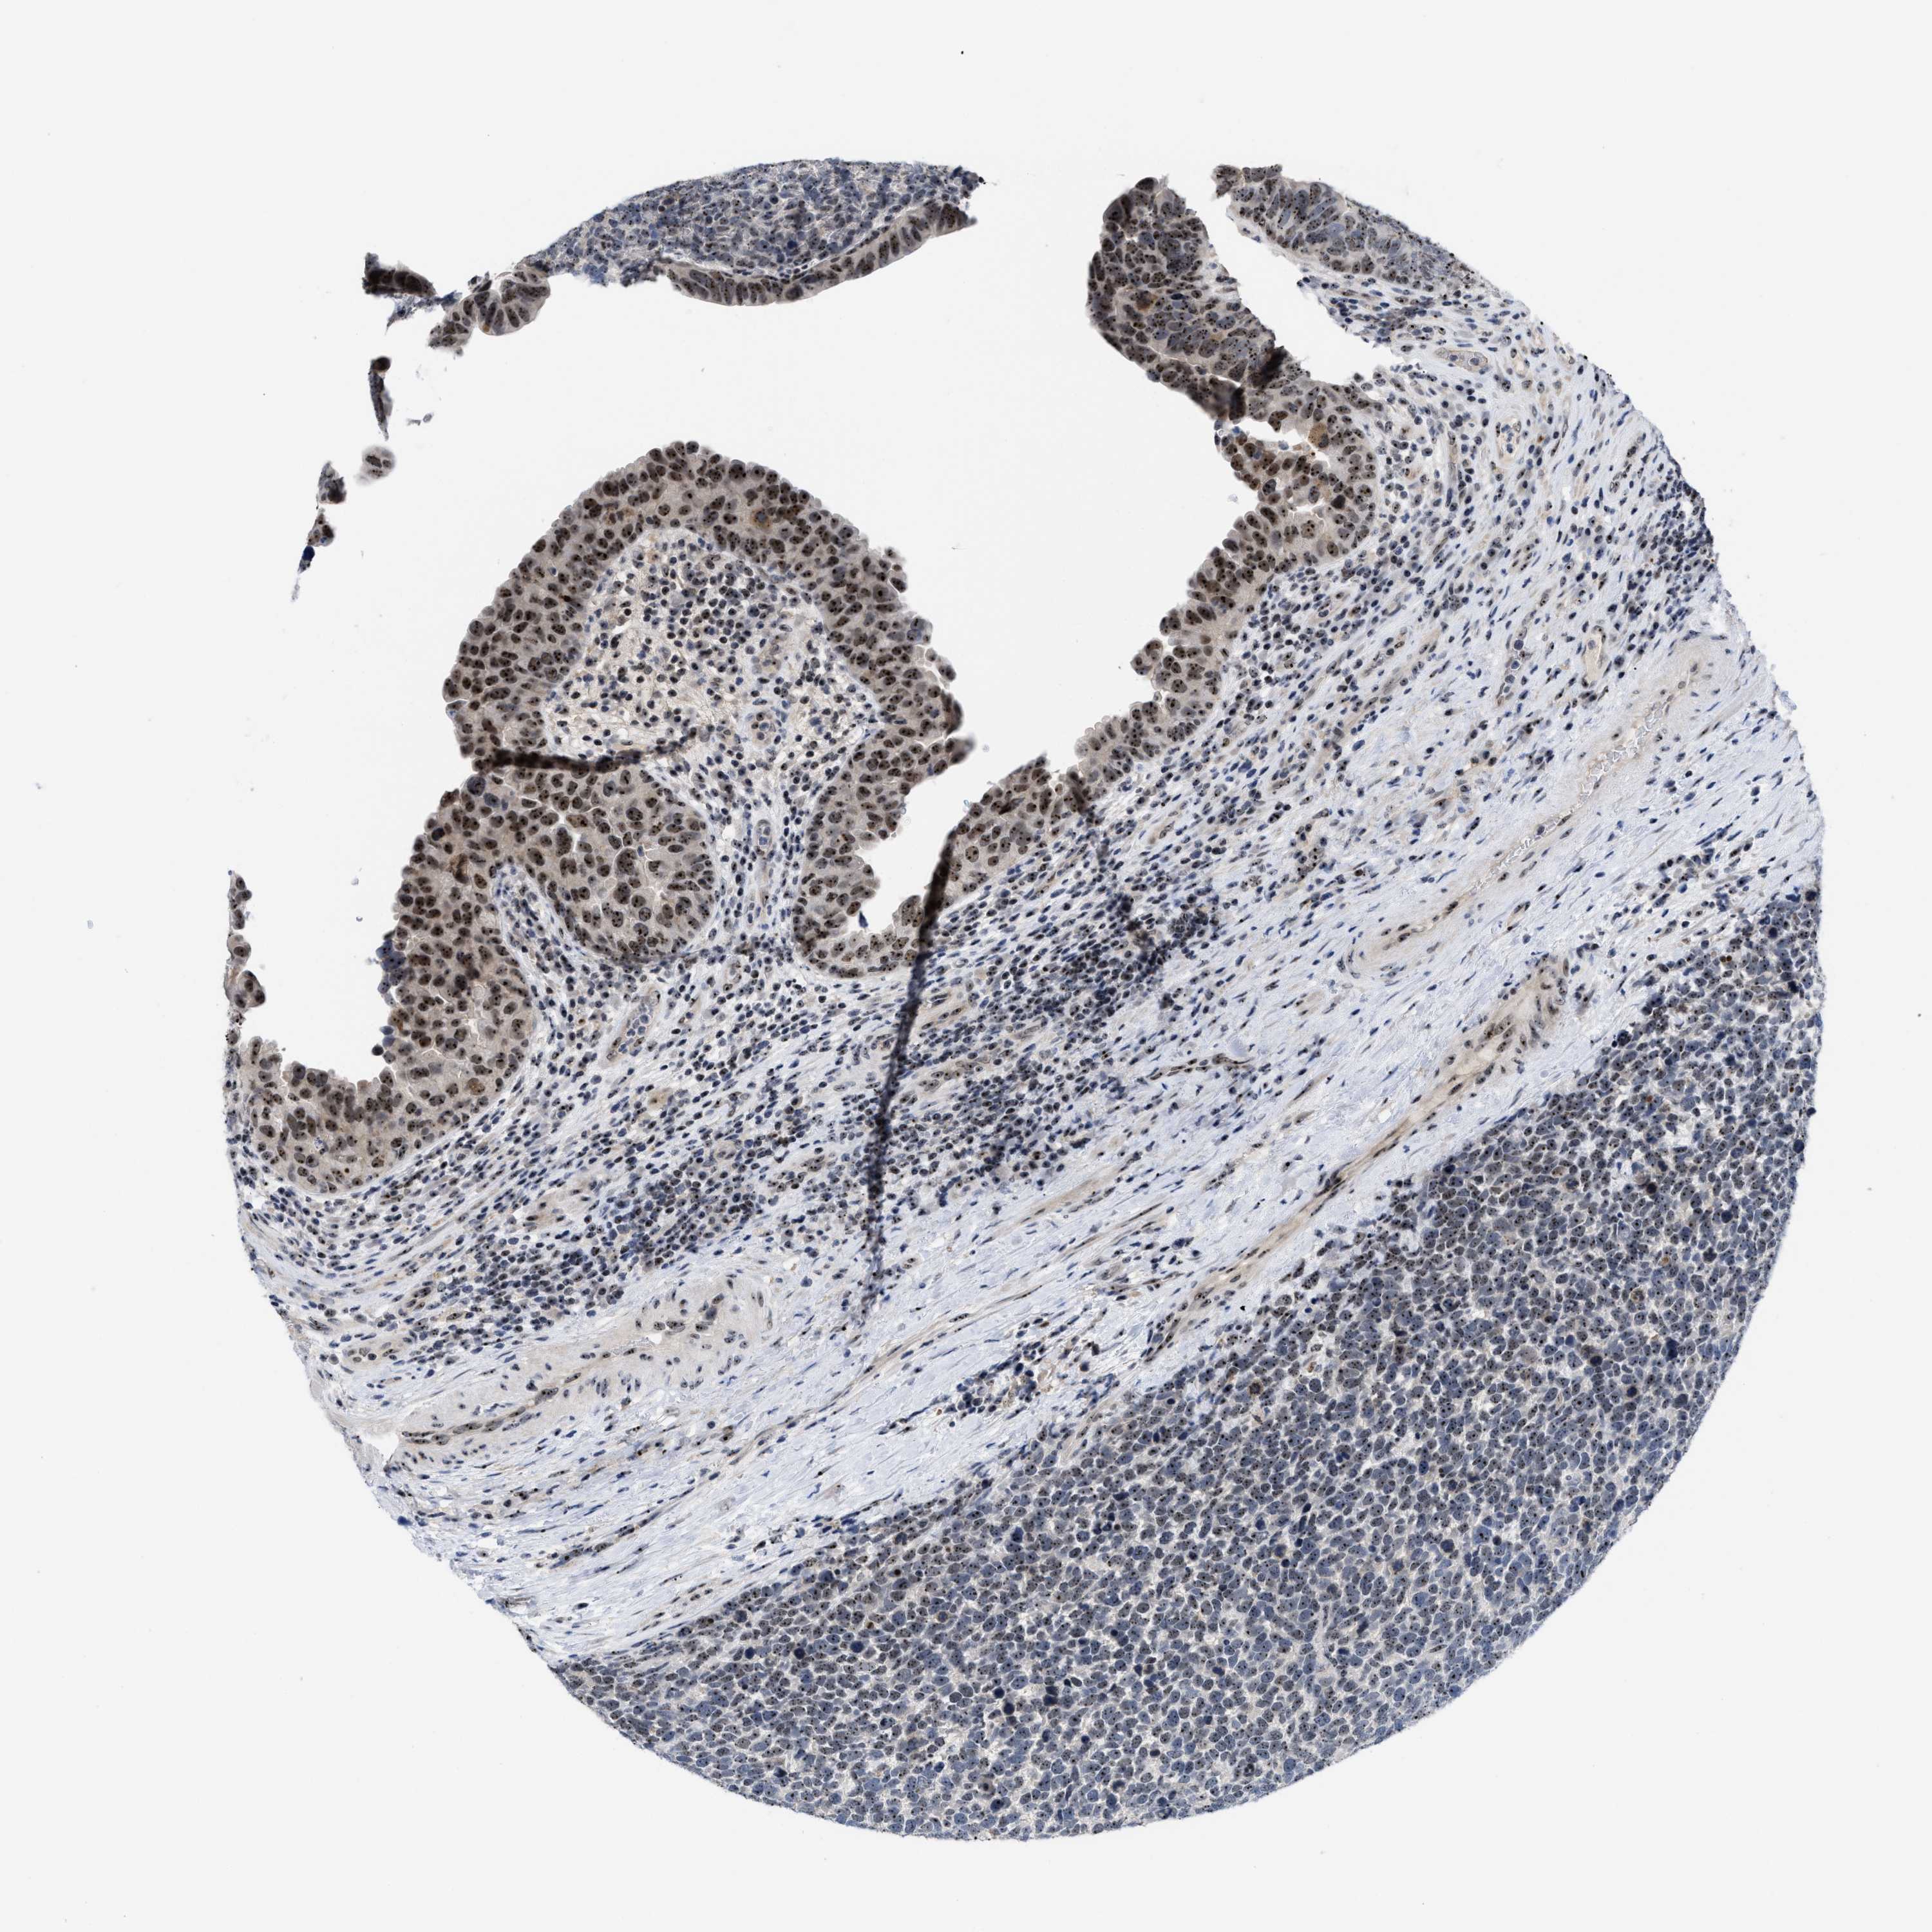

UROTHELIAL CANCER - Protein expressioni

A mouse-over function shows sample information and annotation data. Click on an image to view it in a full screen mode. Samples can be filtered based on level of antibody staining by selecting one or several of the following categories: high, medium, low and not detected. The assay and annotation is described here.

Note that samples used for immunohistochemistry by the Human Protein Atlas do not correspond to samples in the TCGA dataset.

Antibody stainingi

Antibody staining in the annotated cell types in the current human tissue is reported as not detected, low, medium, or high, based on conventional immunohistochemistry profiling in selected tissues. This score is based on the combination of the staining intensity and fraction of stained cells.

Each image is clickable and will lead to virtual microscopy that enables deeper exploration of all samples and also displays staining intensity scores, fraction scores and subcellular localization as well as patient and tissue information for each sample.

Antibody HPA018472

Antibody HPA021062

Urothelial carcinoma, Low grade

Urothelial carcinoma, High grade